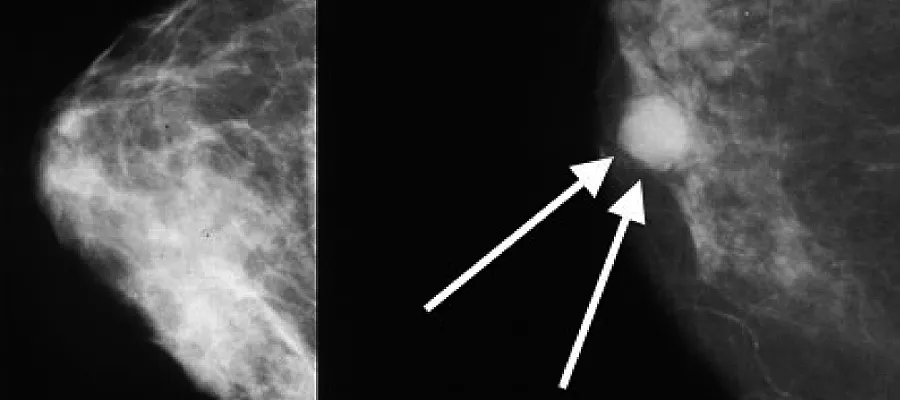

Mammograms showing a normal breast (left) and a breast with cancer (right, white arrows). [Attribution: By Bakerstmd - Own work, CC BY-SA 4.0

Breast cancer represents one of the most common cancer types in modern society. Around 55,200 people are diagnosed with breast cancer in the UK each year - that is around 150 people a day! The risk of breast cancer can be affected by age, family history and lifestyle factors such as obesity and smoking. There has been significant progress in the treatment of breast cancer over the past decades, however many people still die due to breast cancer metastases to the lungs, brain, bone or other places. Therefore it is very important to understand molecular mechanisms involved in breast cancer metastasis and this type of investigations are performed at the MRC Institute of Genetics and Molecular Medicine.